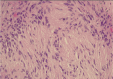

We report a rare case of a 57-year-old female patient with intraluminal tracheal obstruction caused by a benign schwannoma. She underwent successful bronchoscopic resection under general anesthesia, with no complications observed during the post-procedure follow-up. Tracheal schwannomas are exceedingly uncommon, and while conventional treatment involves surgical resection, bronchoscopic techniques, such as laser ablation, can be a valuable alternative, particularly for high-risk patients. Further studies are needed to explore the full potential of bronchoscopic interventions in managing tracheal schwannomas.